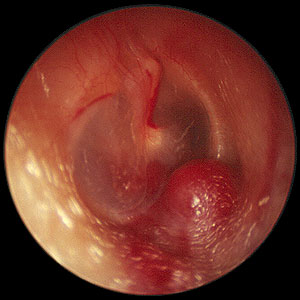

Glomus jugular with Rising sun sign

Presentation: These tumors are slow growing, with very little symptoms. The diagnosis may easily be missed. Infact the average delay between the onset of symptoms and diagnosis varied from 6 years to 15 years. The first symptoms generally follow middle ear involvement is easily overlooked. Pulsatile tinnitus and conductive deafness are the common presenting symptoms. A red mass behind an intact ear drum (rising sun sign) may also be seen. In some 30% of cases cranial nerve palsies are common. Facial nerve is affected most commonly.

Clinical features: Otoscopic examination reveals a characteristic, pulsatile, reddish-blue tumor behind the tympanic membrane that often is the beginning of more extensive findings (ie, the tip of the iceberg). When the drum is examined under a microscope will show a pulsation of the reddish mass behind the drum. On seigalisation the mass blanches. This sign is known as Brown's sign. This is pathognomonic of glomus tumor.